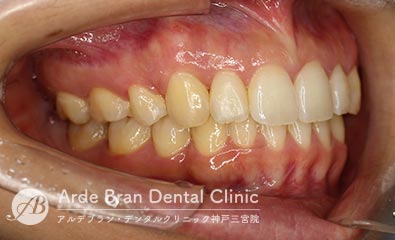

- 叢生/八重歯/歯のがたつき(20代女性 治療期間2年)

- 上下の犬歯の突出と歯のがたつきを主訴に来院されました。特に上下ともに犬歯が大きく前に出ており、噛み合わせに悪影響を及ぼしている状態でした。歯列のスペース不足が顕著であったため、上下左右の第一小臼歯を4本抜歯し、適切な歯列を確保する方針としました。治療では、上下の犬歯を正しい位置へ誘導しながら、全体の噛み合わせを調整。歯列のアーチを整え、前歯のねじれやガタつきも改善しました。治療後は、上下の犬歯が適切な位置に収まり、口元のラインがすっきりと改善。歯並びだけでなく、噛み合わせや清掃性の向上にもつながり、機能的で美しい口元を実現しました。

- 治療前

- 治療後

| 装置名 | インビザライン(マウスピース矯正) |

| 抜歯非抜歯 | 4本抜歯 |

| 治療期間 | 2年 |

| 費用 | インビザラインフル72万円+TAX |